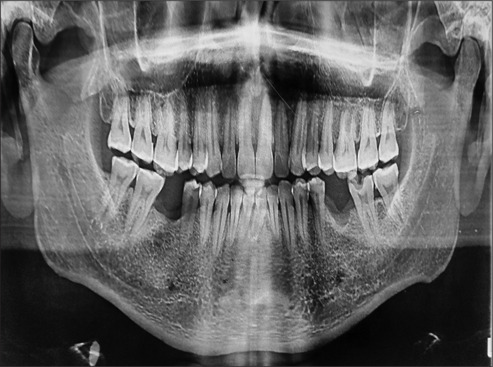

牙髓-牙周(根管-牙周)病变在牙科诊所很常见,患者通常表现为急性牙髓疼痛,常常伴有脓肿形成和牙齿移动。治疗方法一般包括根管治疗(RCT),必要时进行外科手术。本文讨论的是一个值得注意的病例,患者是一名 43 岁的男性,主诉是左上背部疼痛和牙齿松动已持续 3 周。患者接受了一期牙周治疗,随后对 21 号至 25 号牙齿进行了 RCT 治疗。然而,2 周后,患者出现肿胀,于是进行了手术切除和活检。组织病理学分析表明,该病菌为无隔膜的菌丝,具有直角分支,显示为粘孢子菌病。

Endodontic-periodontal (endo-perio) lesions are commonly encountered in dental clinics, with patients typically presenting with acute pulpal pain, often accompanied by abscess formation and tooth mobility. Management generally involves root canal treatment (RCT) and, if required, surgical intervention. This article discusses a notable case of a 43-year-old male patient who presented with a chief complaint of pain and loose teeth in the upper left back region for the past 3 weeks. Phase I periodontal therapy was initiated, followed by RCT of teeth #21 to #25. However, 2 weeks later, the patient presented with swelling, prompting surgical excision and biopsy. Histopathological analysis revealed nonseptate hyphae with right-angle branching, indicative of mucormycosis.